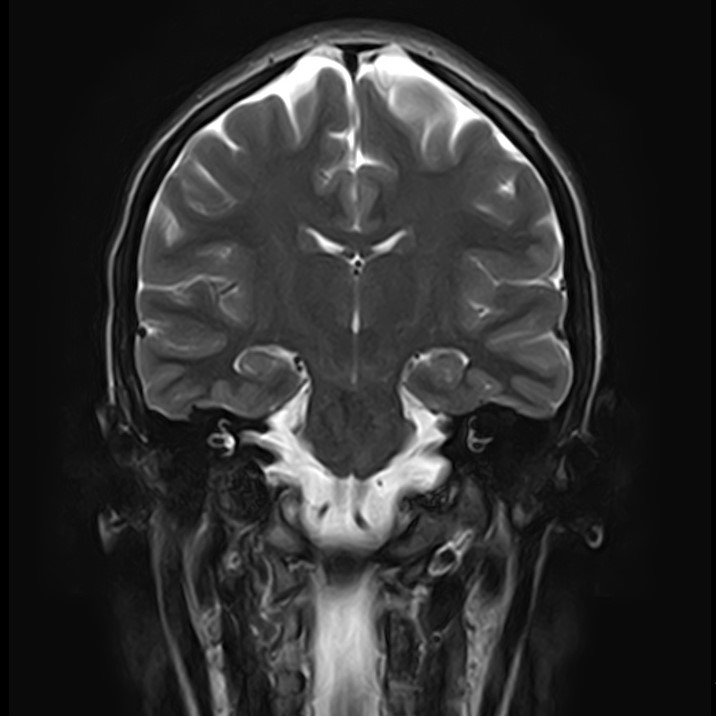

В клинике «Доступная медицина» можно пройти комплексное обследование, включающее в себя два протокола сканирования близко расположенных друг от друга анатомических областей – шейного отдела позвоночника и головного мозга.

Сканирование проводится на современном высокопольном магнитно-резонансном томографе закрытого типа TOSHIBA VANTAGE TITAN 1,5 Тесла, который делает послойные срезы в разных плоскостях с шагом от 1 мм и на основе полученных данных создает трехмерные изображения превосходного качества. Метод исследования позволяет в мельчайших подробностях визуализировать состояние всех структур головного мозга и шейного отдела позвоночника, что дает возможность выявлять патологические изменения на ранних стадиях и назначать своевременное лечение.